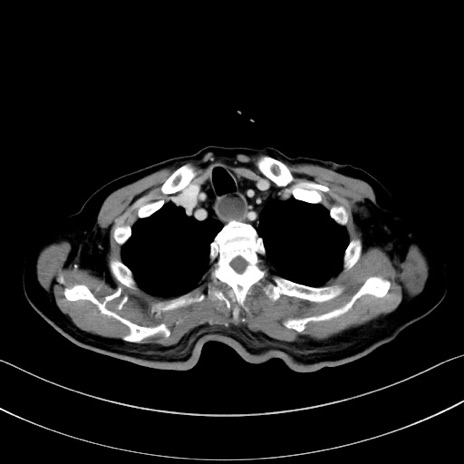

症例28(横断像)

【症例】60歳代男性

【主訴】嘔吐

【現病歴】胃癌にて胃全摘後。食思不振が悪化し、夜中に嘔吐することがある。

【既往歴】胃癌、胃全摘、脾摘、胆摘後

【データ】WBC 5900、CRP 10.56